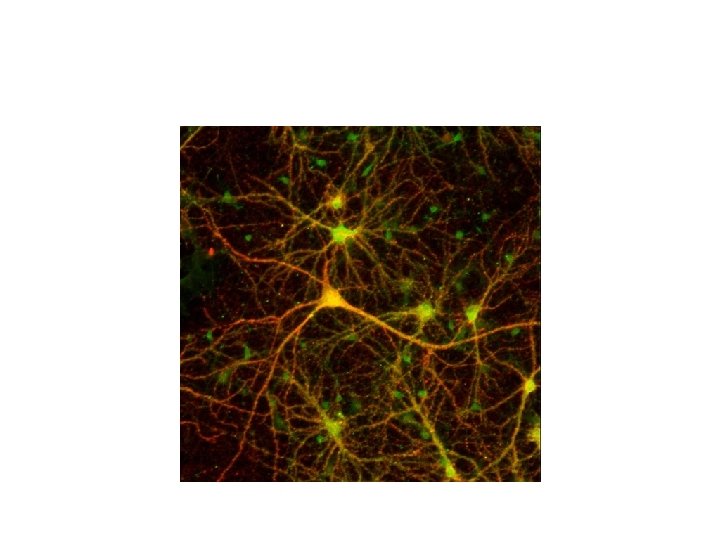

Beauty in the nervous system?

The Basis of the Nervous System • Neurons – Single cell unit of the nervous system – 10 billion in the brain alone – Receives, processes and transmits information • Each neuron in the brain received signals from thousands of other neurons.